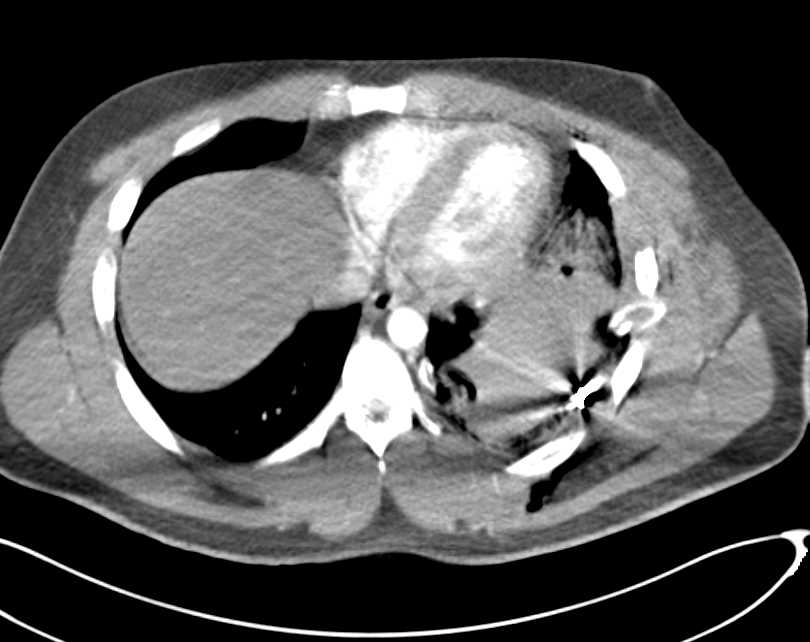

Trauma with Pulmonary Contusion and Rib Fractures Trauma Case Studies

from www.ctisus.com